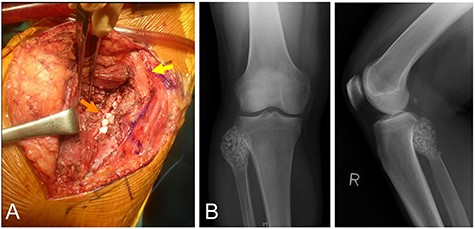

Resection was performed with the patient in the lateral position, and the common peroneal nerve was identified under the fascia. The posterior surface of the proximal fibula was exposed by retracting the soleus muscle from the posterior cortex (Fig. 2A). The cortex over the lesion was fenestrated, and the lesion was curetted. After curettage of the lesion, the cavity was filled with ethanol for 5 minutes as adjuvant therapy, for the purpose of decreasing a possible recurrence. Then, β-tricalcium phosphate particles were implanted (Fig. 2B). A local recurrence was not observed at 12 months postoperatively, and bone incorporation was seen. The range of motion in the knee was not restricted on distal flexion, and there were no complications.

The same patient as in Fig. 1. Posterior approach to the proximal fibula. Note the common peroneal nerve was not dissected from the fibular head (yellow arrow), and β-tricalcium phosphate (β-TCP) particles were implanted from the posterior (orange arrow) (A), with retraction of the soleus muscle posteriorly. Postoperative plain radiographs after β-TCP particles were implanted in the cavity (B).